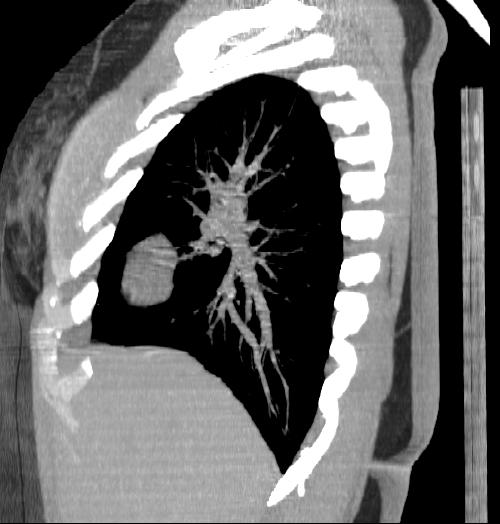

New CT images (without contrast) for 40 year old female with silicone breast implants. Formal diagnosis is expected soon. Images from 2010 can be seen here http://radiology-images.blogspot.com/p/40-year-old-female-silicone-implants.html